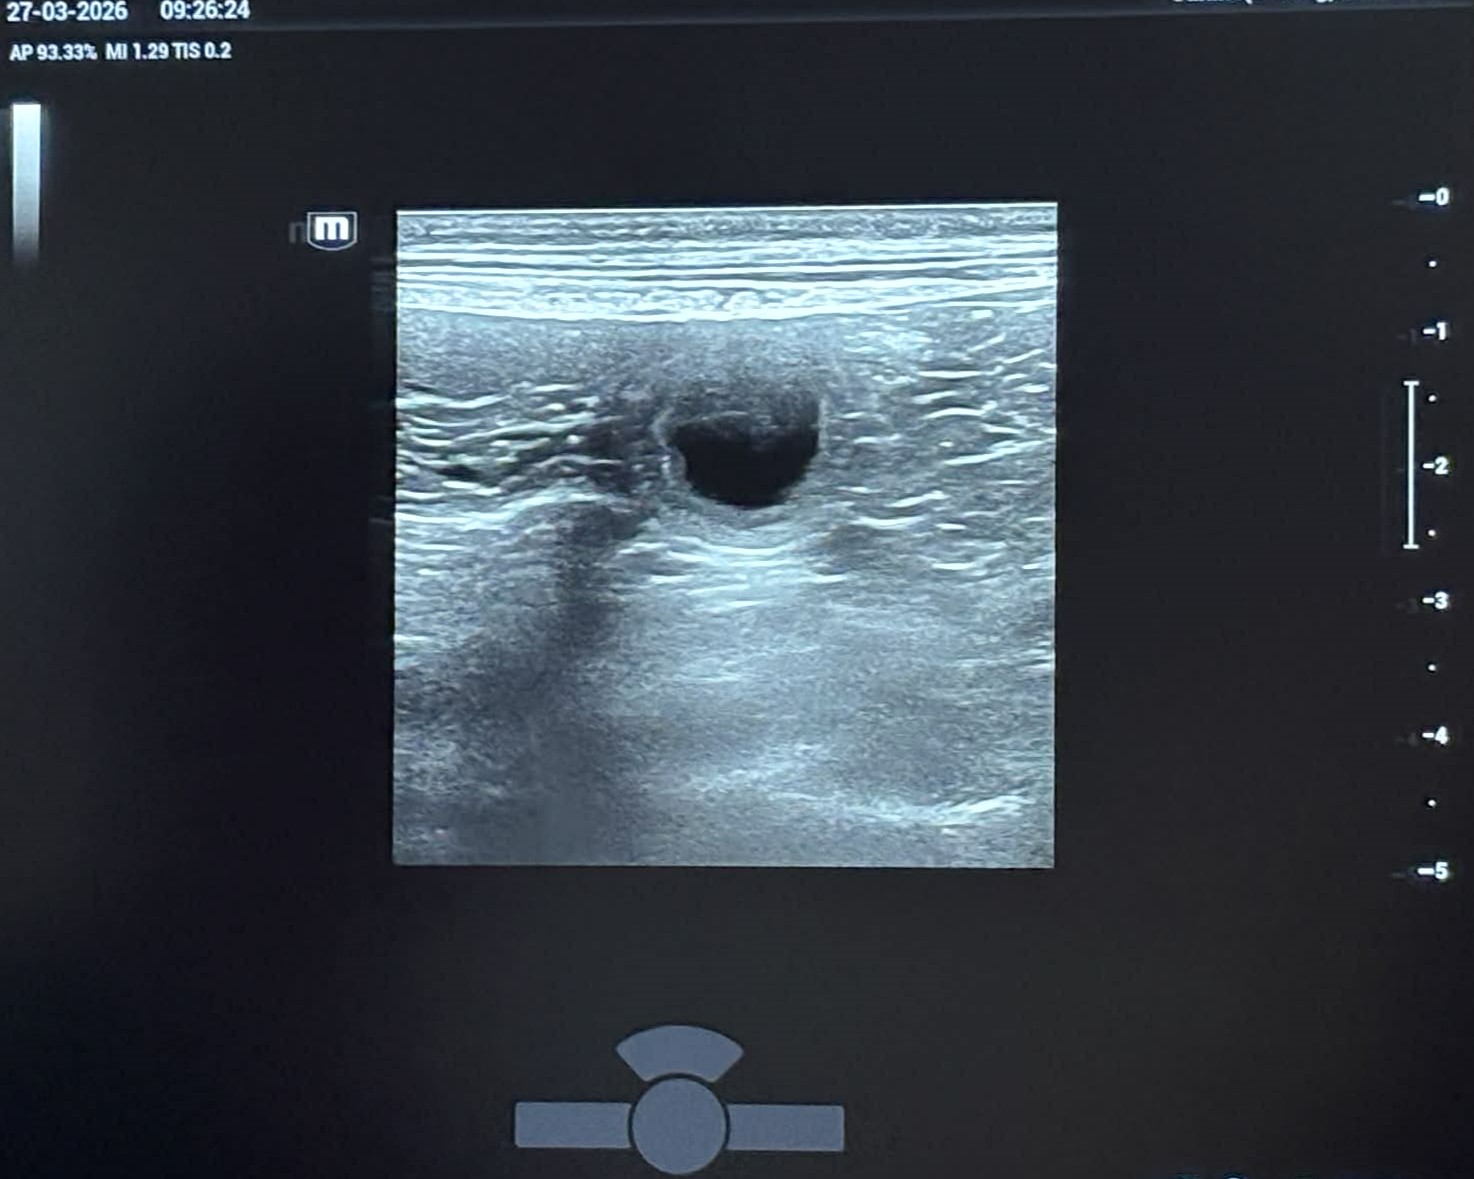

Lola er blevet scannet, og hun er med hvalpe. Hendes apetit er øget og hendes mave er voksende. Hun er blevet meget mere kærlig og kælen.